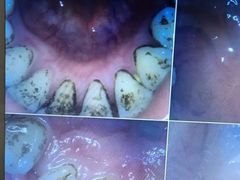

• 好大夫口腔(广州店)

• -好大夫口腔(广州店)

jiaoshen君君 | 23-11-17

报错